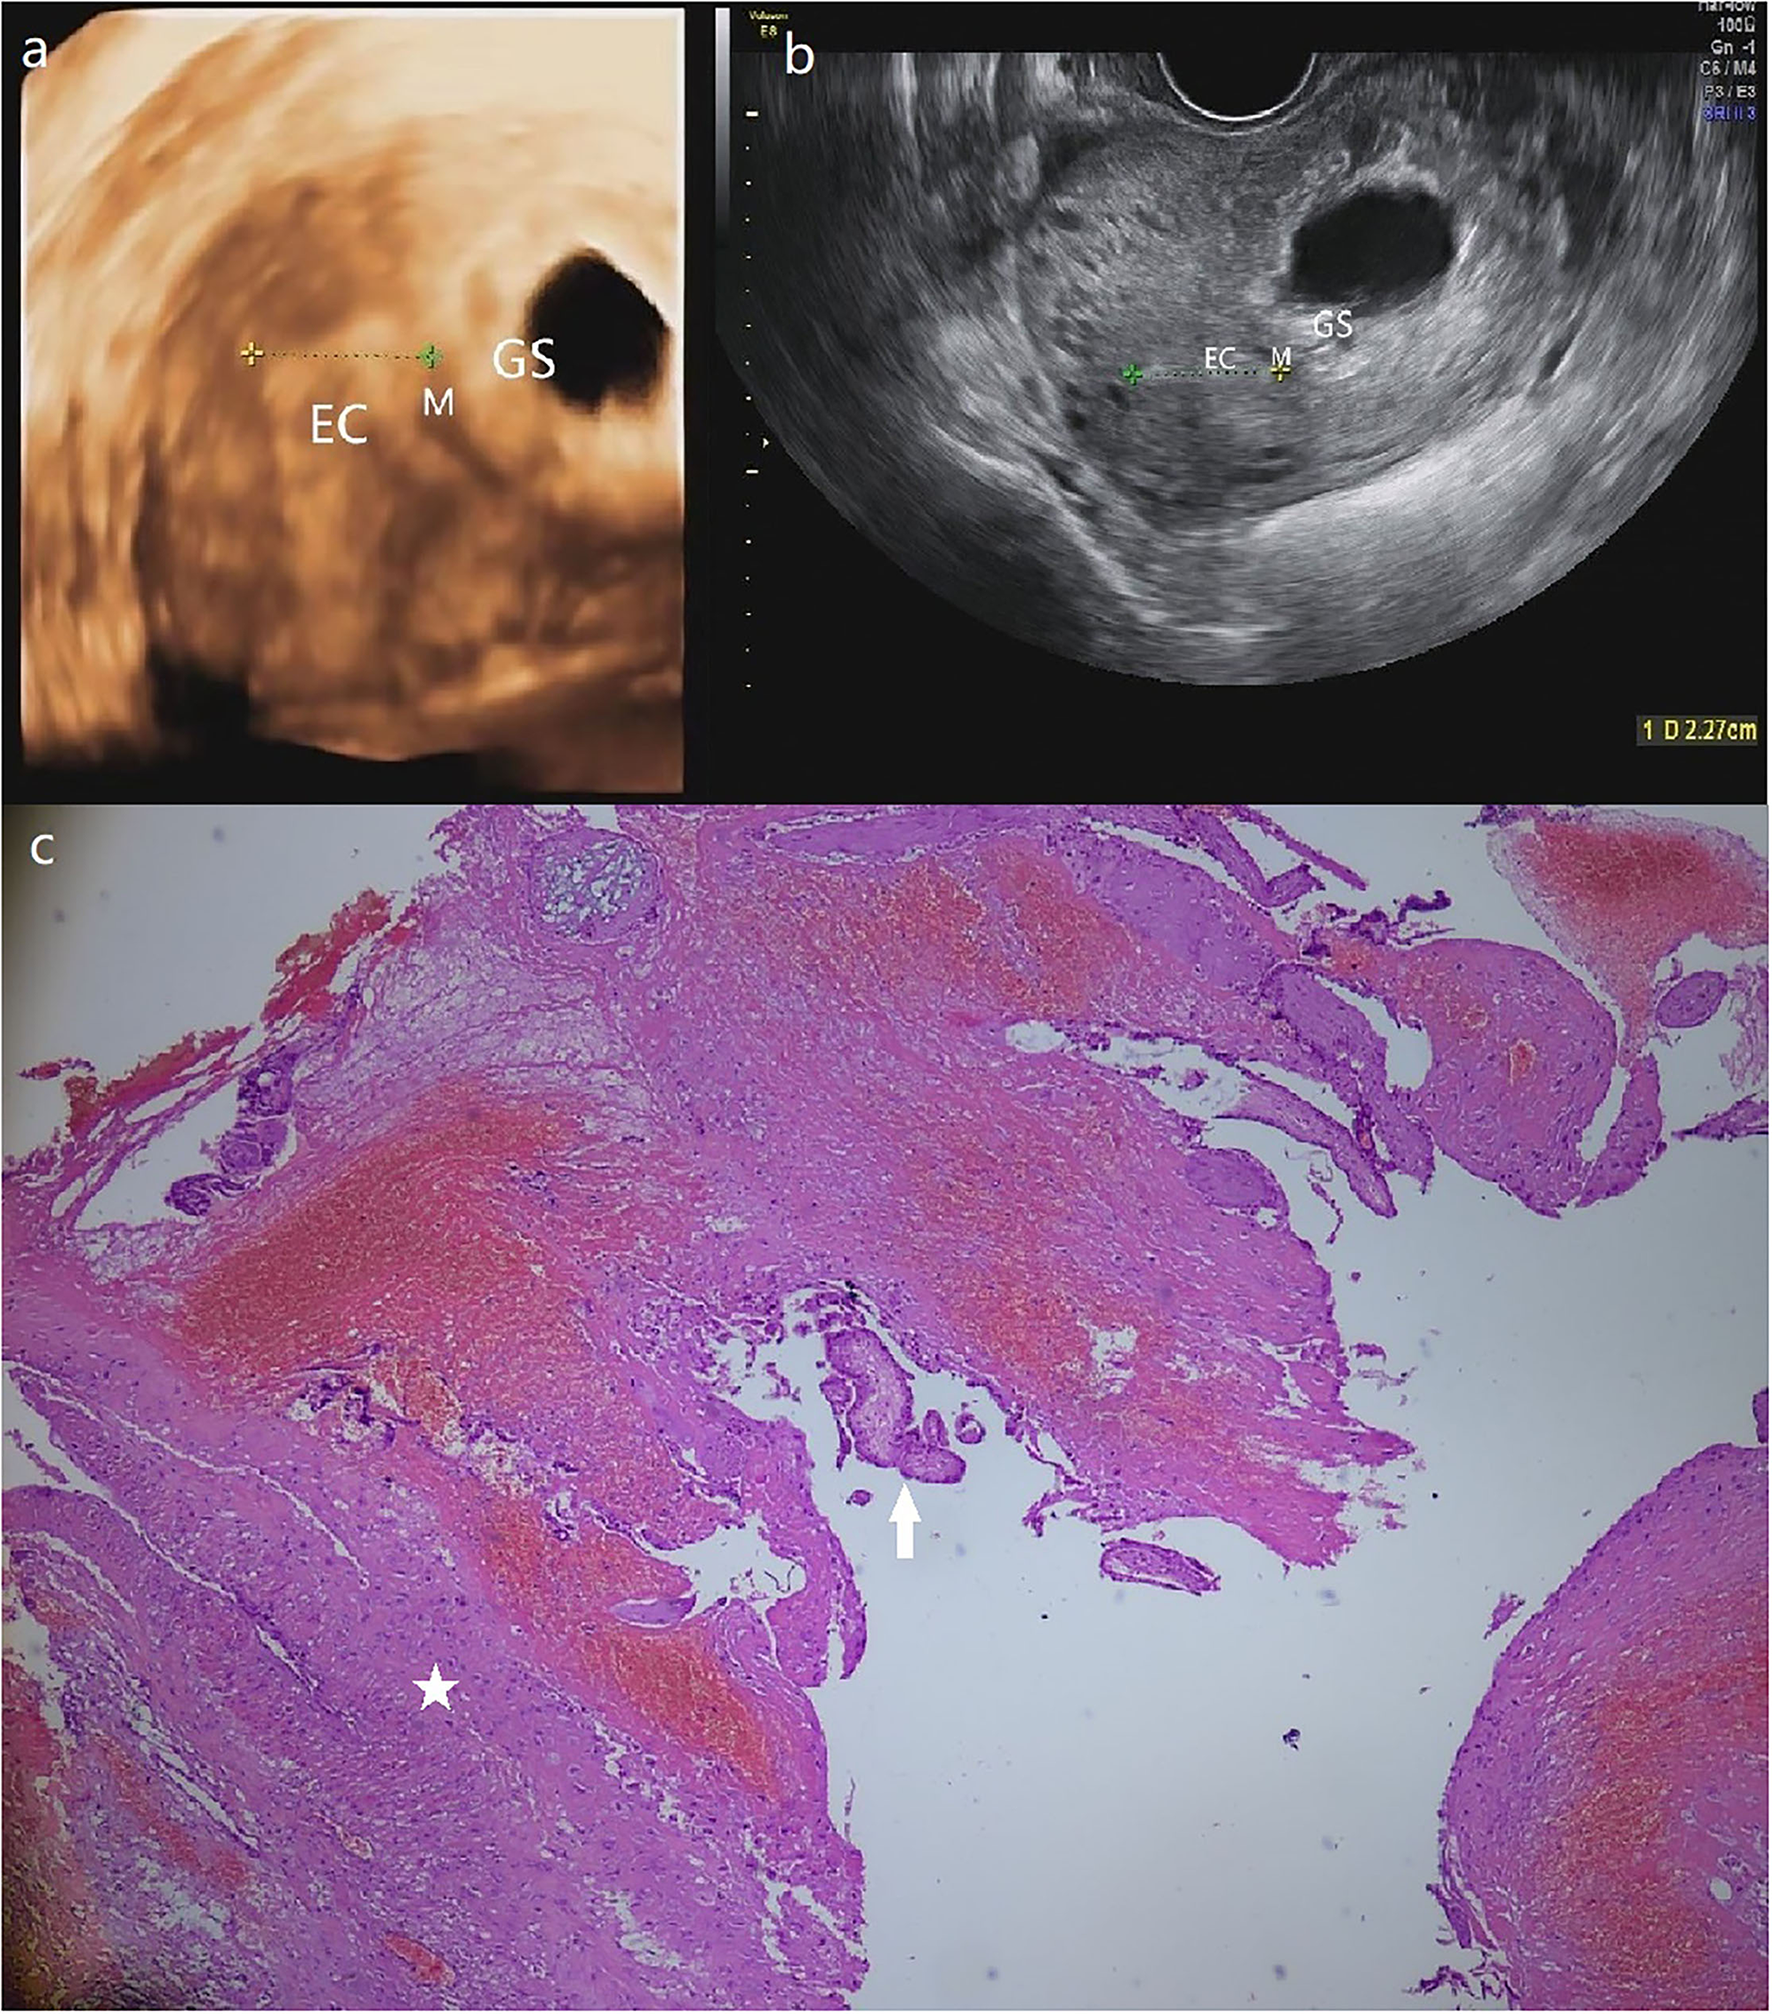

Figure 3

(a) The GS in a size of 4.9*3.4 cm is detected in a heterogeneous echo mass of 6.1*4.5 cm at the left posterior uterine wall near the left corner of the 3-D ultrasound. (b) Transversal section image in 2-D ultrasound demonstrates the intramural pregnancy and shows that the GS has no communication with EC. (c) The pathological result shows the myometrium (star) and the chorionic villus (arrow). (Patient 3, GS, gestational sac; M, myometrium; EC, endometrial cavity).